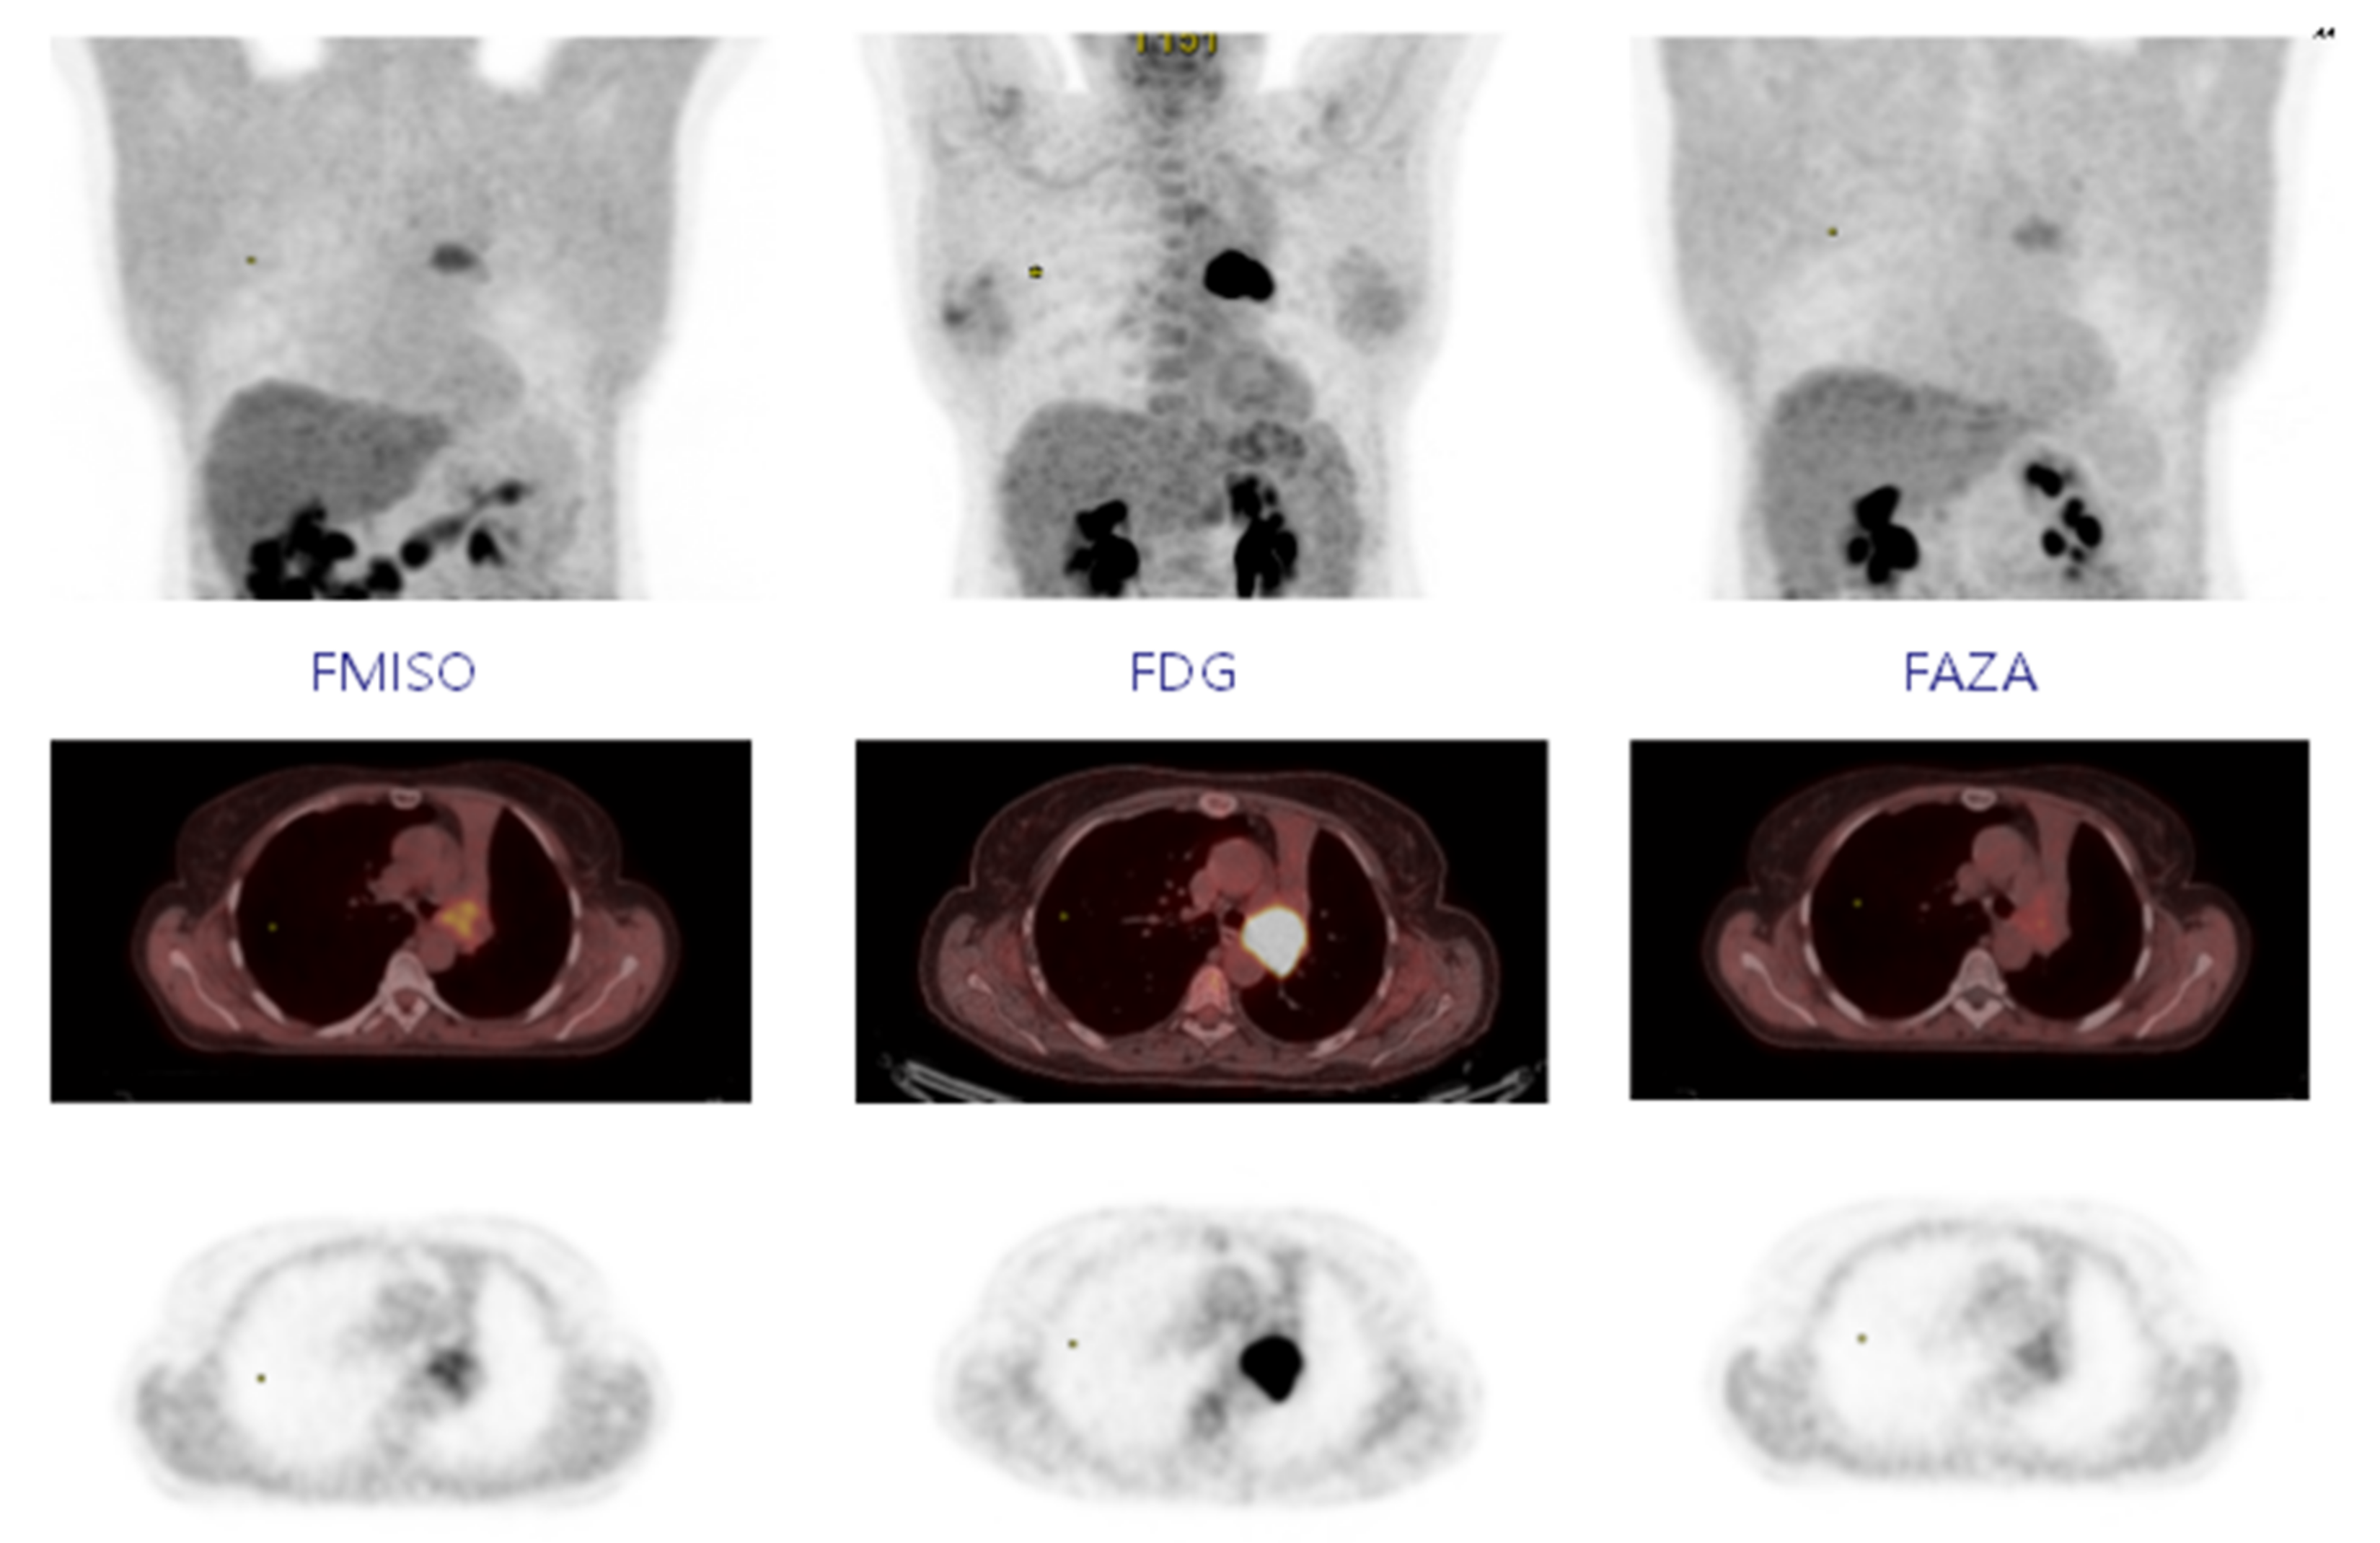

4.2. PET Results

4.3. Overlap Fraction, Parametric Results, and Immunohistochemistry Results